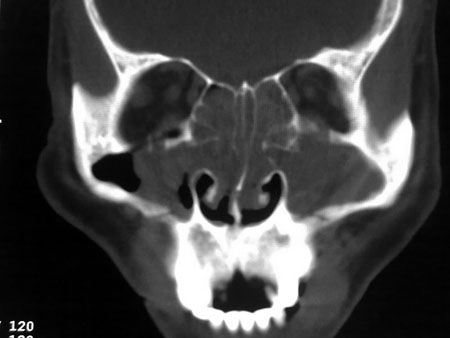

标题: CT21563:M,49,反复鼻塞流脓涕2年余,双侧鼻腔少量水样分 [打印本页]

标题: CT21563:M,49,反复鼻塞流脓涕2年余,双侧鼻腔少量水样分

息肉

双侧鼻息肉,全付鼻窦炎,鼻中隔偏曲。

1)考虑双侧鼻腔及右侧上颌窦息肉。2)全组副鼻窦炎,并左侧额窦粘液囊肿突入左侧眼眶及左侧前颅窝,右侧上颌窦积液。3)鼻中隔偏曲。

(注:上述左右序号可能全反)

双侧鼻息肉,全付鼻窦炎,鼻中隔偏曲;左侧眼眶内上壁可见一类圆形软组织影,占位)建议平扫眼眶

1)考虑双侧鼻腔及右侧上颌窦息肉。2)全组副鼻窦炎,并左侧额窦粘液囊肿突入左侧眼眶及左侧前颅窝,右侧上颌窦积液。3)鼻中隔偏曲。

1)考虑双侧鼻腔及右侧上颌窦息肉。2)全组副鼻窦炎,并左侧额窦粘液囊肿突入左侧眼眶及左侧前颅窝,右侧上颌窦积液。3)鼻中隔偏曲。

1)考虑双侧鼻腔及右侧上颌窦息肉。2)全组副鼻窦炎,并左侧额窦粘液囊肿突入左侧眼眶及左侧前颅窝,右侧上颌窦积液。3)鼻中隔偏曲。

1)考虑双侧鼻腔及右侧上颌窦息肉。2)全组副鼻窦炎,并左侧额窦粘液囊肿突入左侧眼眶及左侧前颅窝,右侧上颌窦积液。3)鼻中隔偏曲。

1)考虑双侧鼻腔及右侧上颌窦息肉。2)全组副鼻窦炎,并左侧额窦粘液囊肿突入左侧眼眶及左侧前颅窝,右侧上颌窦积液。3)鼻中隔偏曲。

1)考虑双侧鼻腔及右侧上颌窦息肉。2)全组副鼻窦炎,并左侧额窦粘液囊肿突入左侧眼眶及左侧前颅窝,右侧上颌窦积液。3)鼻中隔偏曲。

1)考虑双侧鼻腔及右侧上颌窦息肉。2)全组副鼻窦炎,并左侧额窦粘液囊肿突入左侧眼眶及左侧前颅窝,右侧上颌窦积液。3)鼻中隔偏曲。

1)考虑双侧鼻腔及右侧上颌窦息肉。2)全组副鼻窦炎,并左侧额窦粘液囊肿突入左侧眼眶及左侧前颅窝,右侧上颌窦积液。3)鼻中隔偏曲。